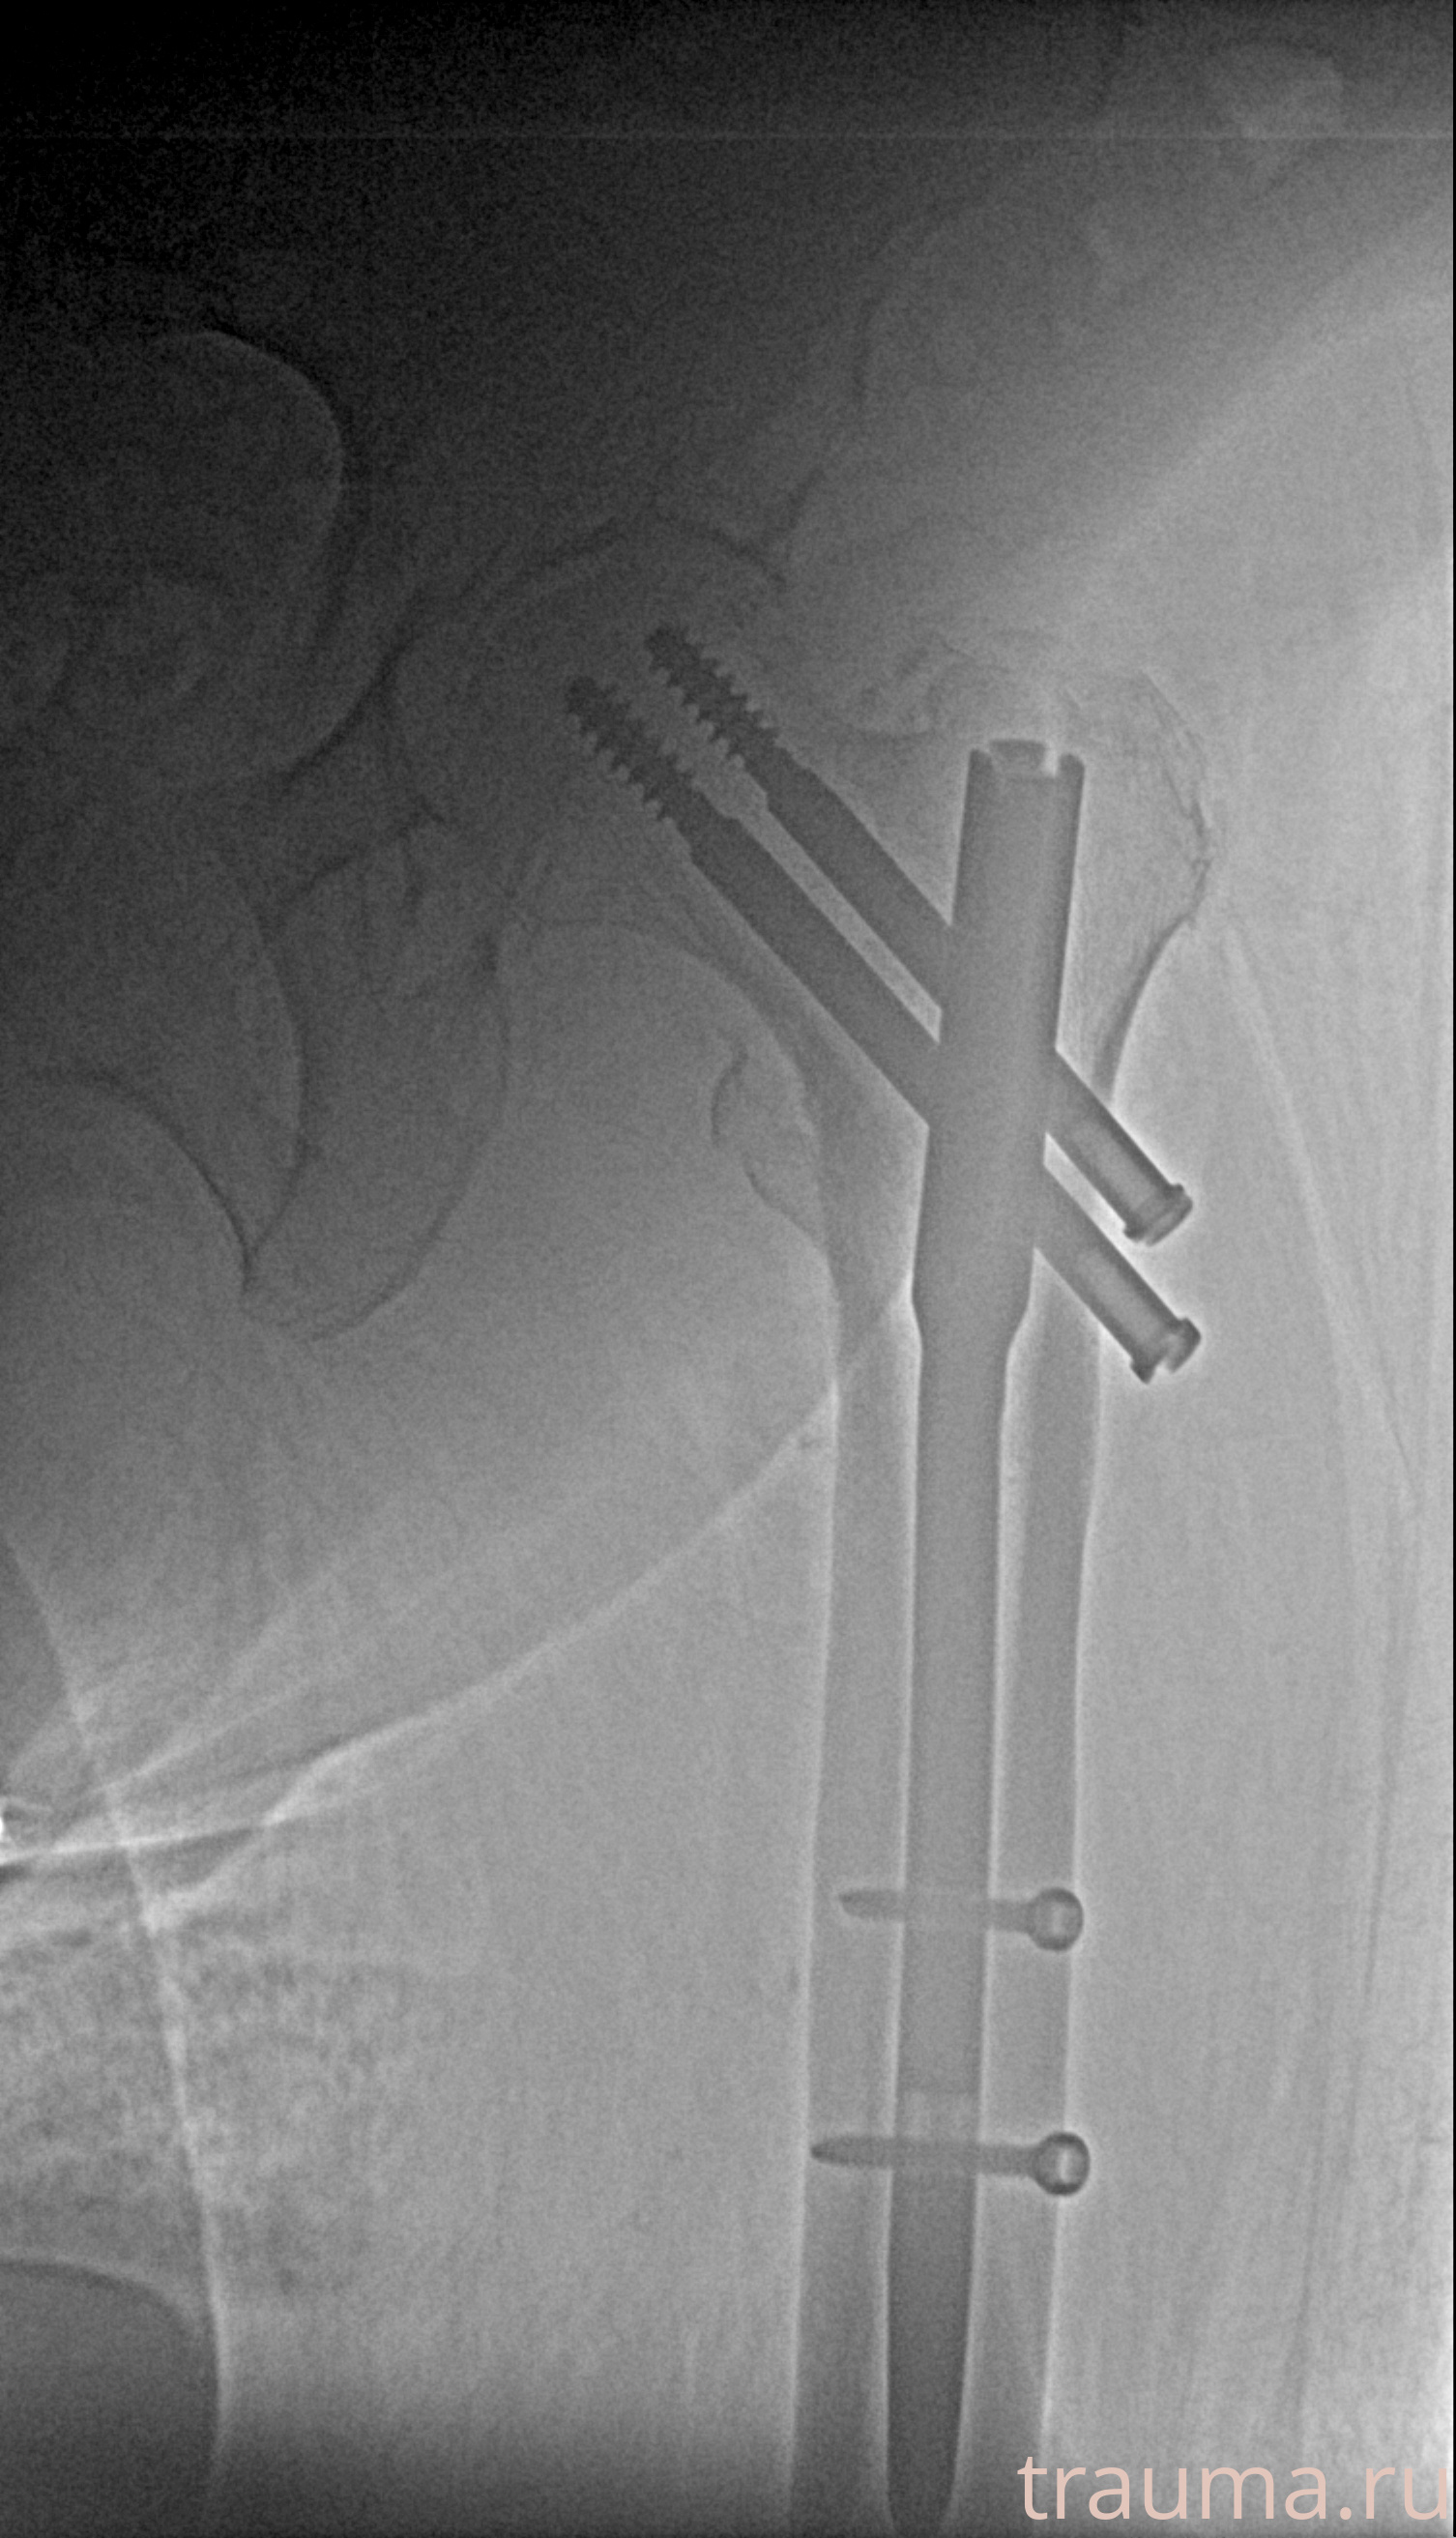

Рентгенограммы

Рентген на дому: по вашему адресу приезжает врач-рентгенолог, травматолог-ортопед с мобильным рентгеновским аппаратом, проводит диагностику травмы или заболевания, делает необходимые рентгенограммы, дает рекомендации по дальнейшему лечению. Получить качественные снимки в домашних условиях возможно благодаря уникальной методике, разработанной МосРентген Центром для института  Склифосовского